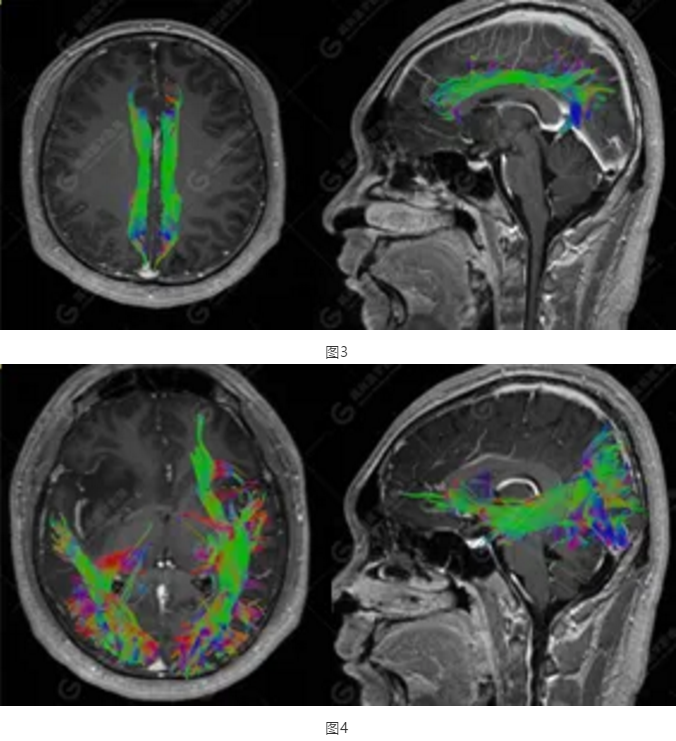

以上為DTI成像,圖1為皮質(zhì)脊髓束,圖2為胼胝體束,圖3為扣帶回束,圖4為額枕束。DTI成像示右側(cè)額枕束前部明顯受壓、部分未見(jiàn)顯示;胼胝體束、雙側(cè)扣帶束、皮質(zhì)脊髓束及左側(cè)額枕束形態(tài)可,纖維束未見(jiàn)明顯破壞,未見(jiàn)明顯稀疏減少。

2.DTI成像示右側(cè)額枕束前部明顯受壓、部分未見(jiàn)顯示。